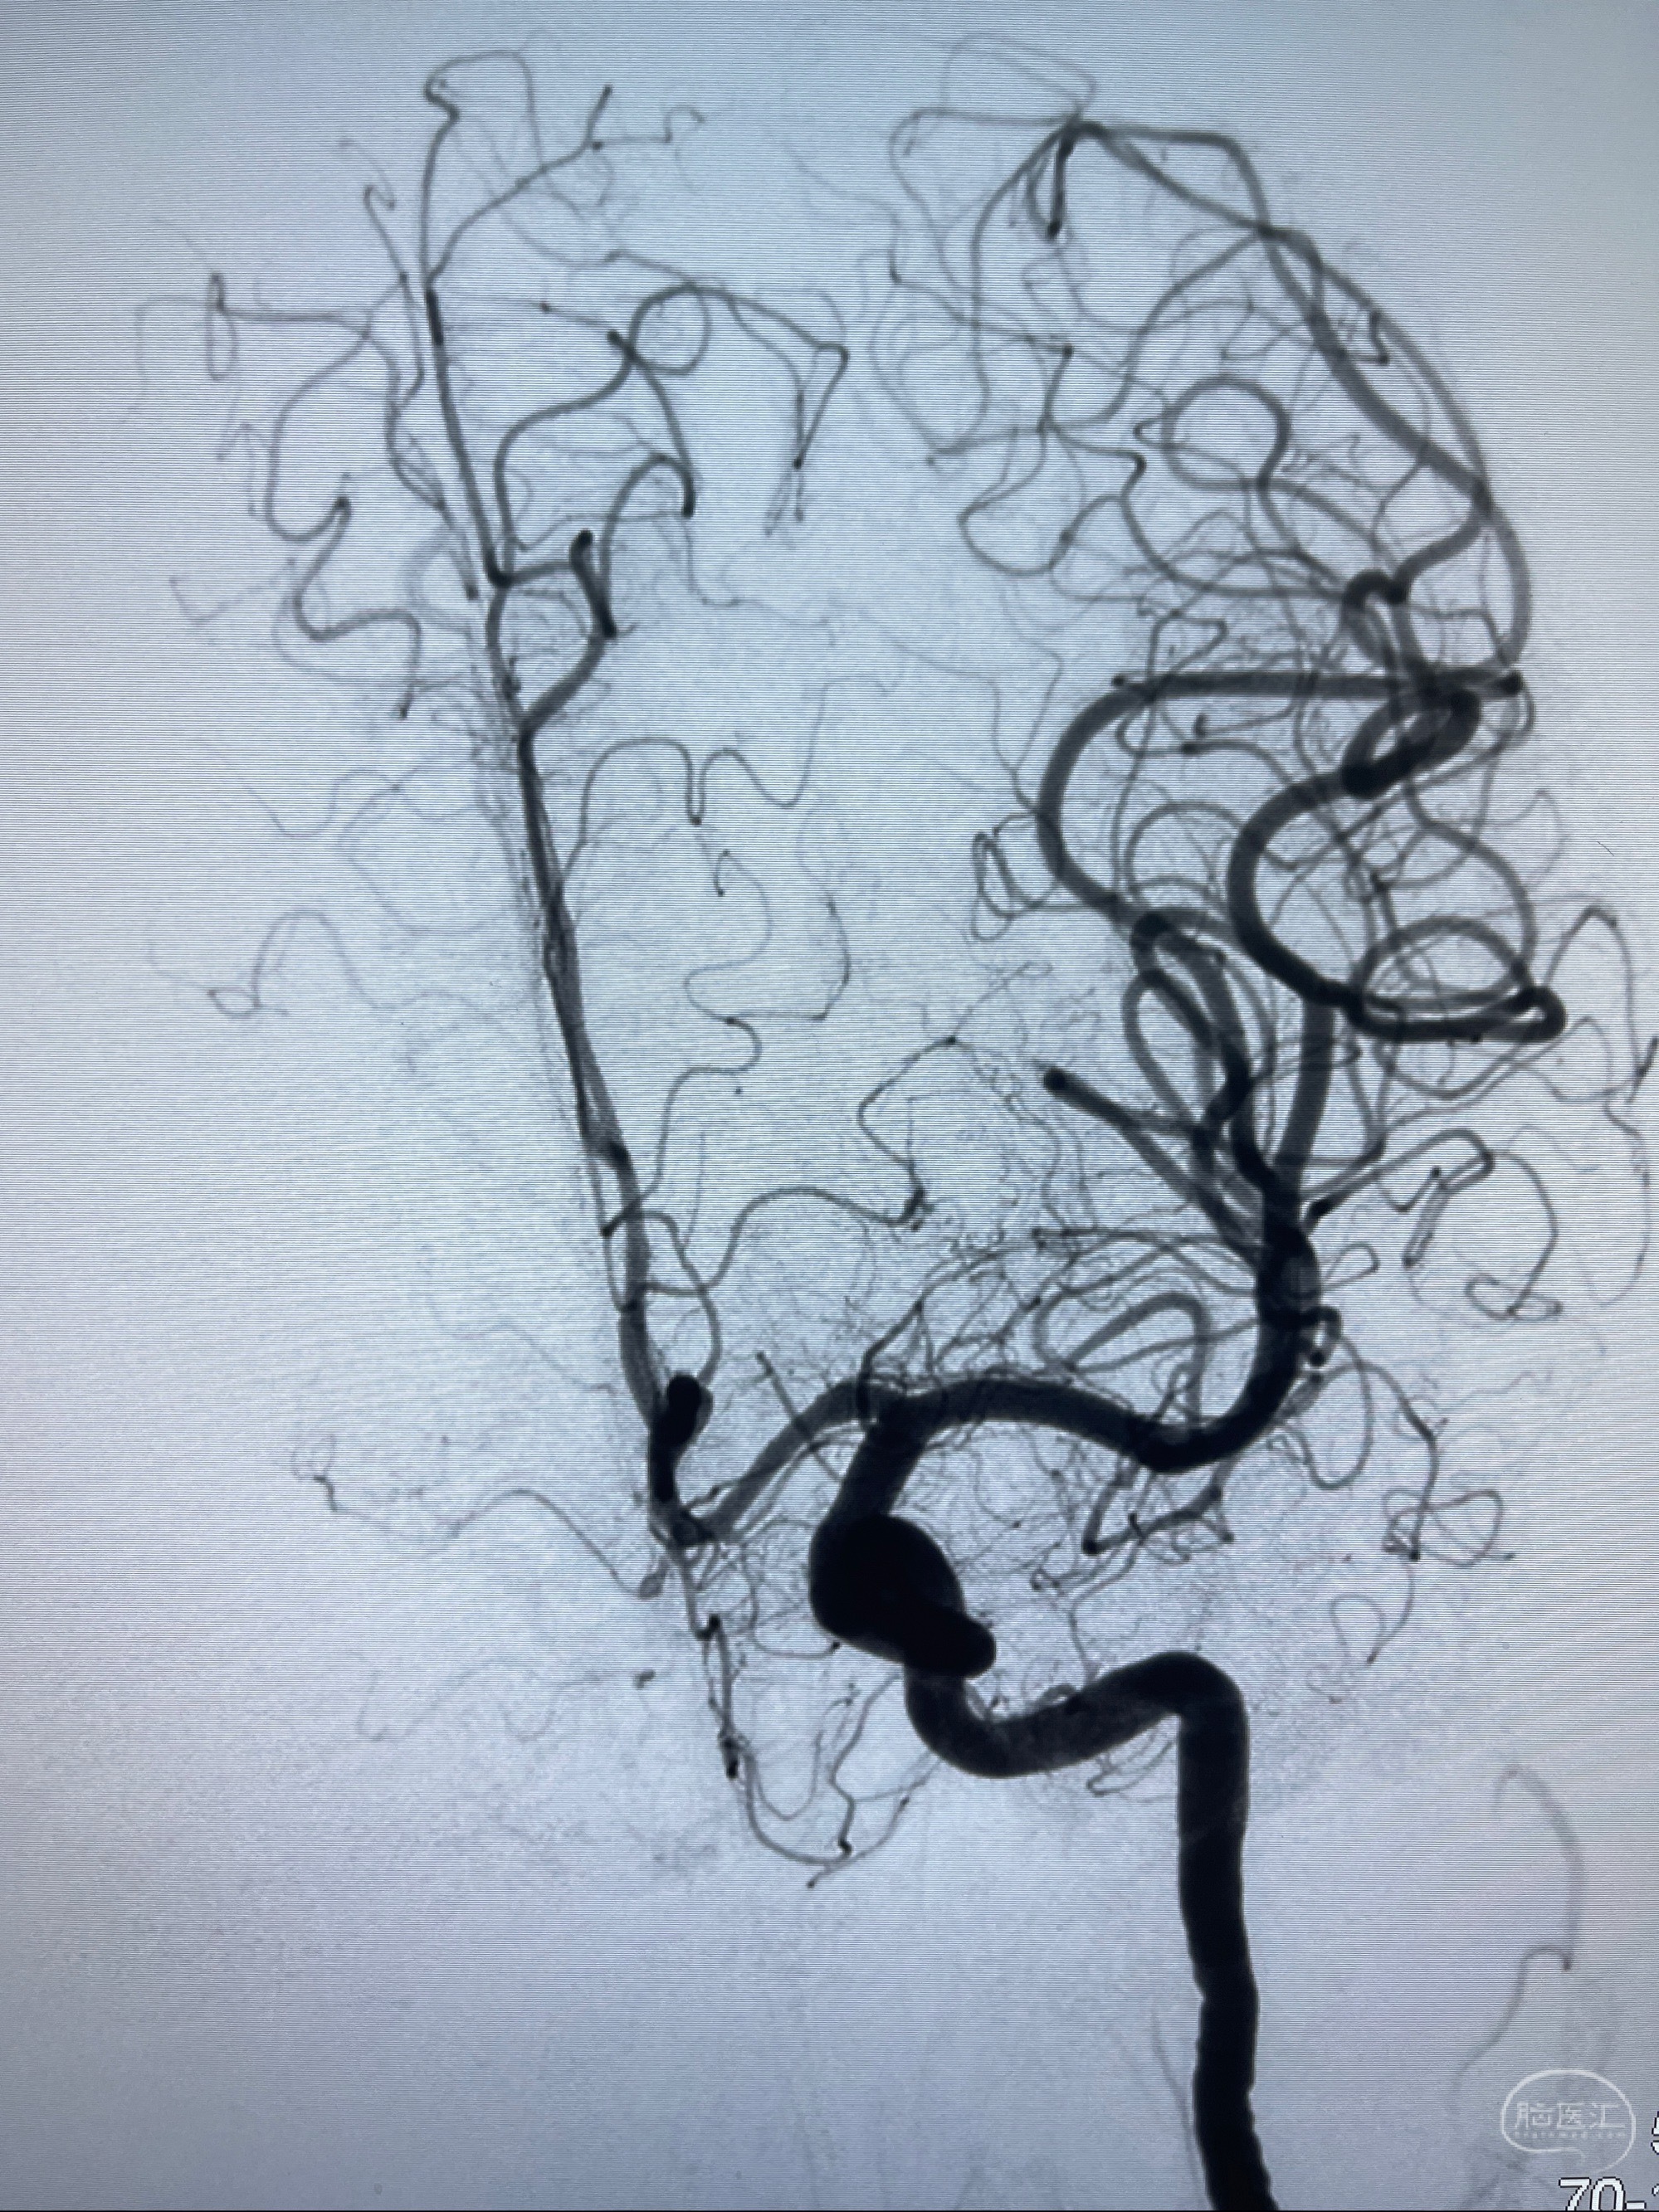

2023-07-27全脑血管造影:双侧颈内动脉眼动脉段动脉瘤,右侧较大

2023-08-01全麻下行双侧颈眼动脉瘤支架辅助栓塞

- pipeling4.5-20mm

- pipeline 4.0-20mm